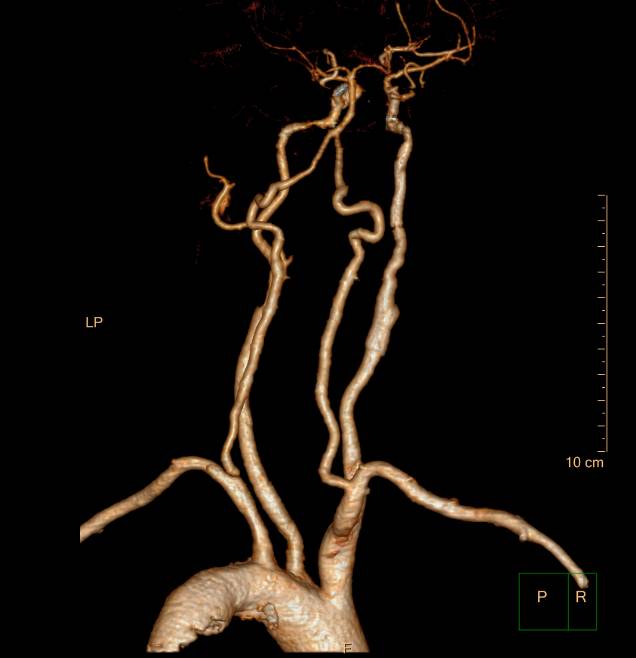

术前三个月造影:右侧颈内动脉几乎不显影。

术后7天复查CTA右侧颈内动脉通畅,管径较术后增粗。

术前CTA,右侧颈总动脉近端开始闭塞,至颈内动脉颈段。

术后七天CTA示:颈总动脉及颈内动脉较术后增粗。

此次分享两例颈动脉闭塞复合手术开通病例。第一例为颈内动脉长段闭塞,从颈内动脉起始段开始闭塞。患者术前存在眼动脉缺血事件及右侧半球灌注不足。颈内动脉剥脱后,颈内动脉可淡淡显影,为微导管通过创造条件。微导管通过后,顺利完成球囊扩张及支架植入,完全开通右侧颈内动脉。第二例为右侧颈总动脉闭塞患者,虽有颈外动脉代偿,但仍存在TIA及右侧大脑半球灌注不足。经颈动脉内膜剥脱后,造影可见颈总动脉显影,但管腔严重不规则,经球囊扩张及支架植入后,颈总动脉显影好。两例患者术后7天复查颈动脉CTA,均显示颈内动脉起始处较术后造影增粗。